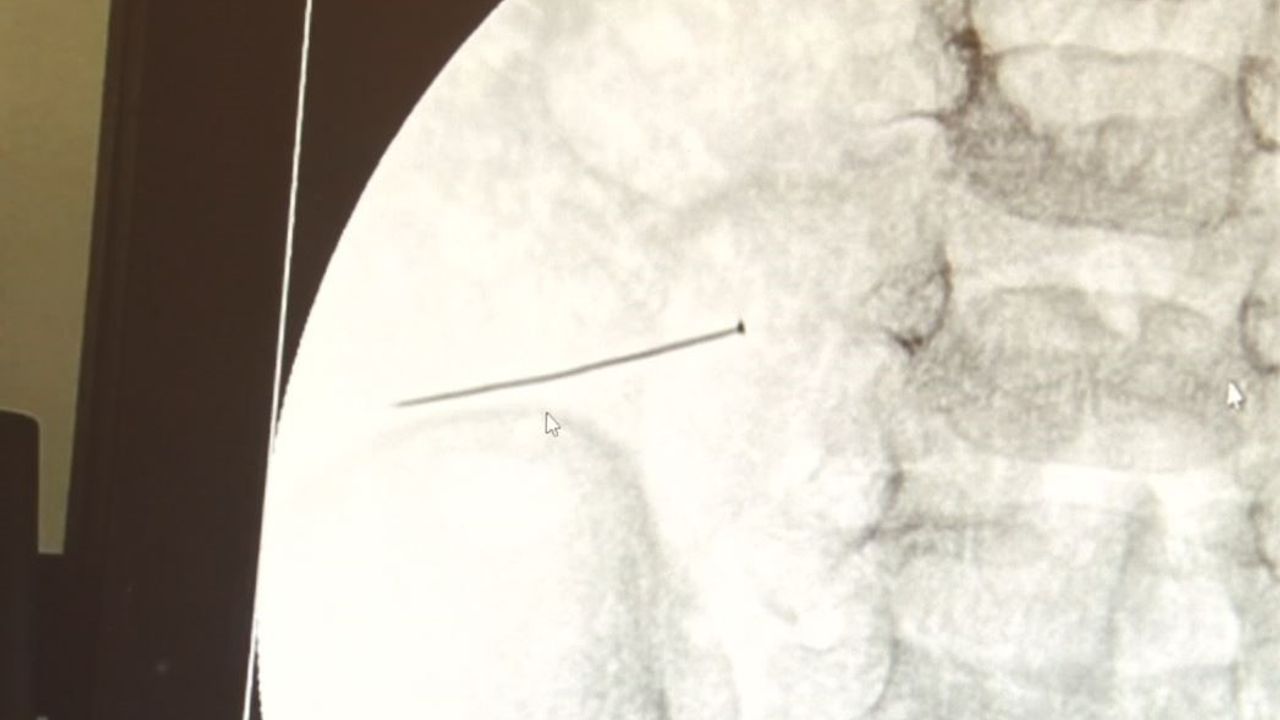

Öte yandan, yaklaşık 3 santimlik toplu iğne filme yansıyan görüntüsüyle gözler önüne serildi.

İstanbul’da 2 yaşındaki çocuk iddiaya göre toplu iğne yuttu sonrasında adeta karın ağrısıyla yerinde duramaz hale geldi. Babaanne, küçük çocuğun şikayetleri üzerine Şehit Prof. Dr. İlhan Varank Sancaktepe Eğitim ve Araştırma Hastanesi’ne götürdü. Burada yapılan tetkiklerde 2 yaşındaki çocuğun ince bağırsağında yaklaşık 3 santimlik toplu iğne olduğu ve bağırsağı deldiği belirlendi. Görüntülemeler sonrası 30 Ekim akşamı Çocuk Cerrahisi Kliniği Eğitim ve İdari Sorumlusu Doç. Dr. Sefa Sağ ve ekibi hemen ameliyata girdi. Başarılı operasyonla iğne olduğu noktadan alınırken aile de rahat bir nefes aldı. Doç. Dr. Sağ ise taburcu edilen hastasının durumuna ilişkin bilgi verirken yabancı cisim yutmalarına karşı ailelere önemli uyarılarda bulundu.

Çocuklarda yabancı cisim yutulmasına yönelik konuşan ve hastasına ilişkin bilgi veren Doç. Dr. Sefa Sağ, "Soluk borusuna kaçması durumunda çocuğun Allah göstermesin ölümüyle veya ömür boyunca yatağa bağımlı kalmasıyla neticelenebilecek sonuçlar doğurabiliyor. Yutulması durumunda da gastrointestinal sistemin herhangi bir yerine takılmadığı müddetçe ekseriyâ yabancı cisimlerin dışarıya çıkmasını bekliyoruz. Yabancı cisim yutulmasını 2 grupta inceleyebiliriz. Sıvı ve katı cisimler olarak sıvı; evde kullanılan kimyasal temizlik malzemelerinin yutulması çok ciddi problemler oluşturabilmekte. Ağızda, yemek borusunda ve midede yanıklar meydana getirebilmekte. Uzun dönemde çocukların hayat kalitesini oldukça etkileyen sonuçlar doğurabilmekte. Katı cisimlerden de ekseriyâ kendiliğinden çıkmasını bekleriz ancak böyle delici, kesici aletlerin yutulmasında ise herhangi bir bağırsağın veya gastrointestinal sistemin bir parçasında delinmeler meydana getirebiliyor. Bu çocuğumuzda da aynen böyle bir hadise meydana gelmişti. Sanırım 1 gün önce ailenin yuttuğunu tahmin ettiği bir yabancı cisim; toplu iğne. Ertesi gün bağırsakta delinmeyle sonuçlanmış ve çocukta da ciddi semptomlar meydana getirmişti. Bu şekilde hasta bize başvurdu. Tetkikler sonucunda yabancı cismi tespit ettik, semptomları ve bulgularına göre de çocuğu ameliyata aldık. Yaklaşık 3 santim boyunda bir toplu iğnenin ince bağırsağı deldiğini, ince bağırsaktaki içeriğin de karın içerisine dolduğunu gördük. Ameliyatı başarılı bir şekilde tamamladık, yaklaşık 1 saat süren bir ameliyattı" dedi.